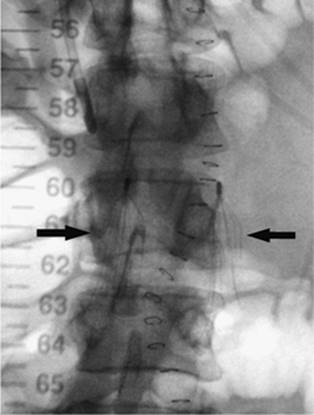

000415

Figure 35.7. A 70-year-old female with progressive pneumothorax following placement of transvenous cardiac pacing device. A: Arrows indicate the partially collapsed left lung following pacing device placement. B: Fluoroscopic image obtained at time of 8 Fr chest tube insertion. The tube was placed slightly lower than the usual apical position to avoid potential damage to the pacing device or wires. C: Following chest tube insertion, the pneumothorax was evacuated with syringe aspiration of the air. Follow-up chest radiograph demonstrates near-completed resolution. The chest tube was connected to Pleur-Evac drainage system.